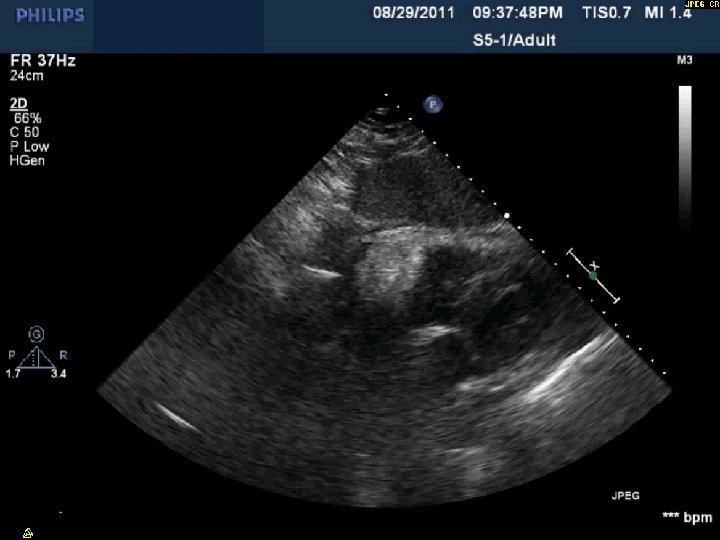

Day 2 No further pericardial drainage, echo without effusion…pericardial catheter pulled Day 3 Enoxaparin

Day 2 No further pericardial drainage, echo without effusion…pericardial catheter pulled Day 3 Enoxaparin for DVT prophylaxis initiated 8 hours later, PEA arrest Echo shows recurrence of effusion and tamponade physiology

Day 2 Stable overnight No further pericardial drainage Echo shows no recurrence of effusion

Day 2 Stable overnight No further pericardial drainage Echo shows no recurrence of effusion In ICU, pericardial pigtail catheter pulled…. . Within 5 minutes, systolic blood pressure drops to <80 and bedside echo confirms recurrence of effusion Emergency pericardiocentesis draws off 650 cc immediately followed by continuous drainage of blood